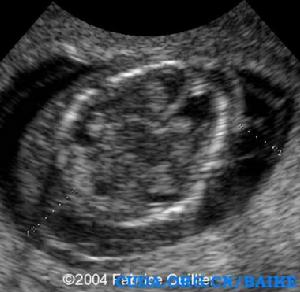

超聲發現:囊性水囊瘤是嚴重X單體的早孕和中孕期典型的徵象。妊娠晚期,孤立的胸腔積液和廣泛的水腫可以發生。最常見的心臟畸形是主動脈弓縮窄。